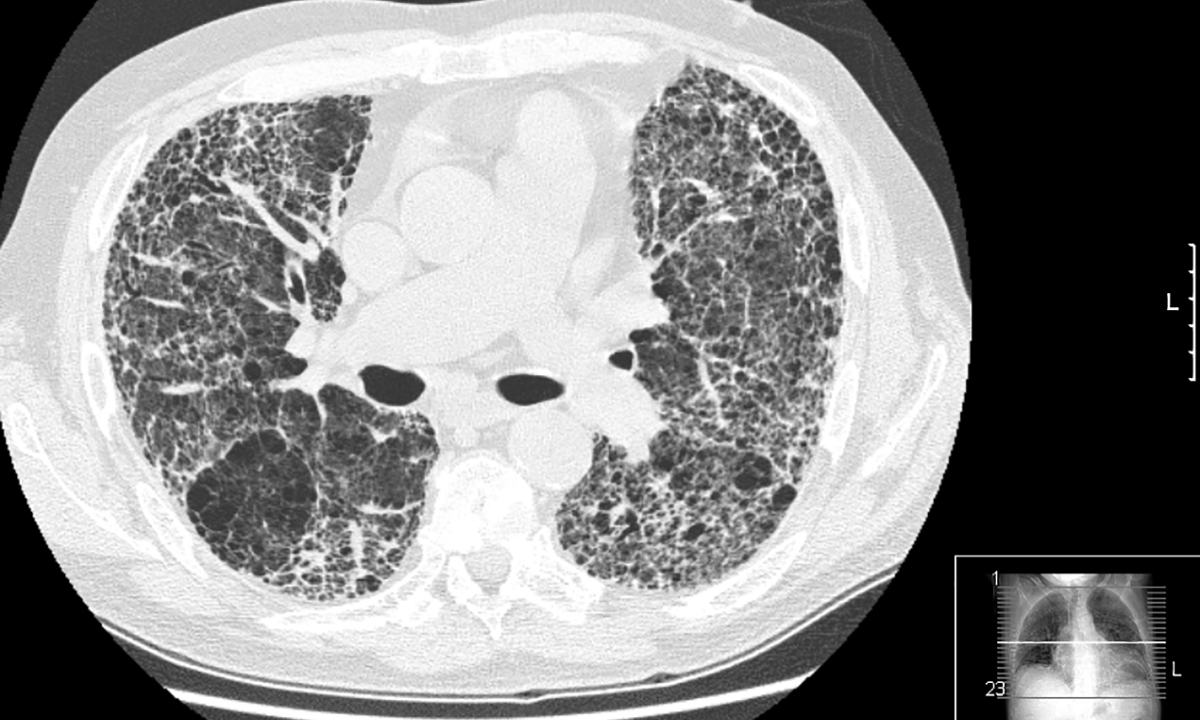

IDIOPATHIC pulmonary fibrosis (IPF), caused by excessive scarring of the lungs, is a particularly nasty disease to get. People with the condition become increasingly breathless and develop a dry, unproductive cough, symptoms which get progressively worse until death intervenes. Patients, who tend to be over the age of 50 years, typically die within 2–5 years of diagnosis.

“That’s something we’ve focused on in the paper,” says Dr Corte. “The problem is that a lot of fibrosis looks the same, so IPF is very easy to misdiagnose. It’s important to get input from a range of specialists to rule out other possible illnesses, which may look similar but in fact can be much easier to treat.”